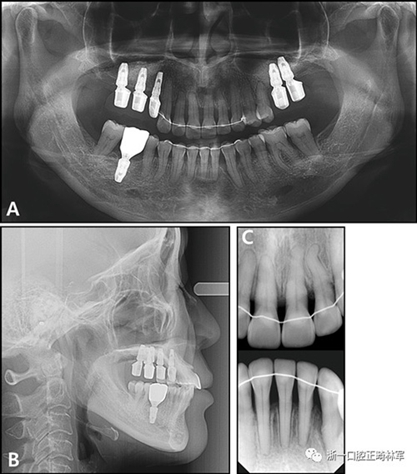

全景X線片顯示了牙槽骨支持的整體下降和下頜左側(cè)側(cè)切牙區(qū)廣泛的骨質(zhì)喪失。頭影測量分析表明是具有正常垂直面形,上頜切牙唇向錯位以及與Rickett‘s E線相關(guān)的上唇前凸的骨性I類關(guān)系(圖3和4;表II)?;颊弑辉\斷為骨骼I類錯合畸形,伴有慢性中度牙周炎和多顆牙齒缺失。

圖3. 治療前X線片:A,牙周治療前的全景X光片; B,牙周治療后的全景X光片; C,側(cè)位X線片; D,根尖片。

治療后全景X線片顯示與初始值相比,沒有顯著的骨喪失。上頜尖牙被推入并向遠中移動,導(dǎo)致在根尖周觀察到尖牙骨水平的改善。在拔除的下頜側(cè)切牙周圍出現(xiàn)嚴重的牙槽骨缺損,并且尖牙近中側(cè)的牙周病引起了骨內(nèi)缺損。在關(guān)閉間隙期間,下頜中切牙和尖牙被移向了骨質(zhì)缺損區(qū)域,并且側(cè)切牙周圍的缺損已被恢復(fù)(圖12)。此外,尖牙的牙齦退縮臨床上也得到了改善(圖13)。

圖12.治療后的X線片:A,全景X光片;B,頭影側(cè)位片;C,根尖片

根據(jù)治療前后的根尖X光片,可以發(fā)現(xiàn)存在3.5mm顯著改善的放射線骨水平(圖15),并且臨床上牙周袋深度減少(表IV)。此外,力的推入性成分在向遠中移動期間誘導(dǎo)了上頜切牙的推入,并且在根尖X線照片上看到牙槽骨水平的改善。同時,如果種植體首先定位在磨牙區(qū)域,則可以通過使用種植體的臨時修復(fù)作為支抗來控制該力學(xué)過程。這種方法的優(yōu)點在于它解決了患者的主訴,即通過逆轉(zhuǎn)上頜前牙的張開和用最小程度的外科手術(shù)取代缺失的后牙進行咬合來重建咬合和美學(xué)。但是當(dāng)施加推入力時,在力作用線上施加一個垂直方向的力是不利的。完成整個治療需要花費很多時間,并且在正畸治療期間臨時修復(fù)體可能被破壞。